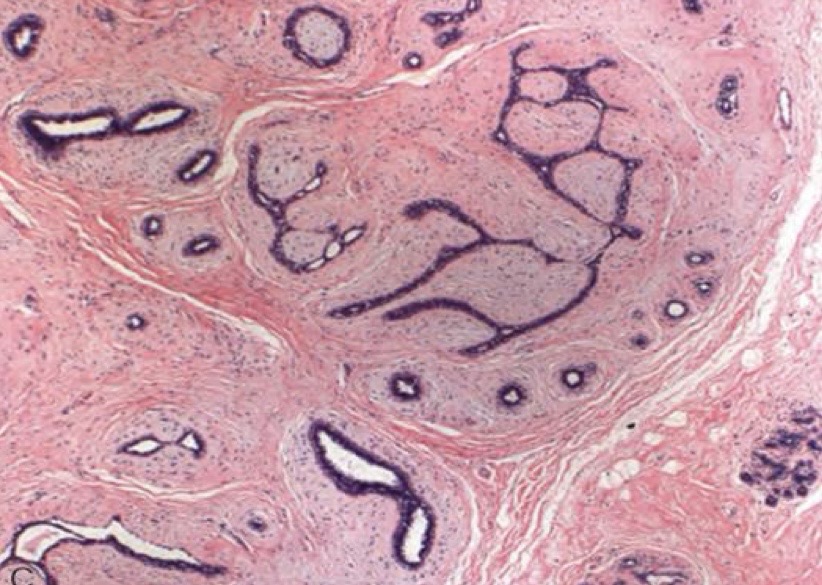

A- Urothelial papilloma

B- Papillary fronds with fibrovascular cores are lined by normal appearing urothelium

C- from benign epithelial tissue